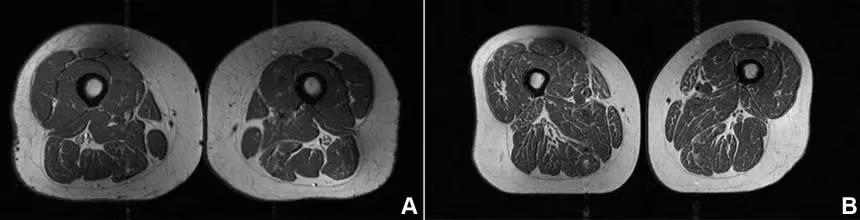

Hình ảnh trên thoạt nhìn giống như một lát thịt bò cao cấp với những đường vân mỡ dày đặc xen kẽ. Nhưng thực ra, đó lại là ảnh chụp MRI phần đùi của một phụ nữ 62 tuổi, người có tới 87% lượng calo tiêu thụ trong năm đến từ thực phẩm siêu chế biến.

Theo Tiến sĩ Zehra Akkaya, nhà nghiên cứu và cố vấn trong nhóm Nghiên cứu Hình ảnh Cơ Xương Khớp Lâm sàng và Chuyển giao tại Đại học California (San Francisco), chế độ ăn của người này chủ yếu gồm ngũ cốc ăn liền, kẹo socola, các loại thanh kẹo và nước ngọt có đường. Những lựa chọn tưởng chừng quen thuộc này lại để lại dấu ấn rõ rệt bên trong cơ thể.

Các vệt mỡ len lỏi giữa và trong từng sợi cơ không chỉ là một hình ảnh bất thường, mà còn có thể là dấu hiệu cảnh báo những vấn đề sức khỏe nghiêm trọng. Akkaya cho biết nhóm của bà đã phân tích mối liên hệ giữa thực phẩm siêu chế biến và lượng mỡ tích tụ trong cơ ở những người có nguy cơ loãng xương khớp gối.

Điều đáng nói là ngay cả khi tỷ lệ tiêu thụ thấp hơn, tác động vẫn có thể thấy rõ. Trong nghiên cứu, một phụ nữ 61 tuổi khác chỉ tiêu thụ khoảng 29% calo từ thực phẩm siêu chế biến cũng xuất hiện tình trạng mỡ xen kẽ trong cơ đùi, dù mức độ nhẹ hơn.

Khi so sánh cụ thể, các nhà nghiên cứu nhận thấy một chi tiết khá bất ngờ. Người phụ nữ 61 tuổi chỉ ăn khoảng 29,5% thực phẩm siêu chế biến có chỉ số BMI cao hơn một chút (32,6) và cũng ít vận động hơn.

Trong khi đó, người phụ nữ còn lại dù có BMI thấp hơn (31,8) nhưng lại tiêu thụ tới 87,1% thực phẩm siêu chế biến. Kết quả cho thấy người ăn nhiều thực phẩm siêu chế biến hơn lại có lượng mỡ tích tụ trong cơ đùi cao hơn rõ rệt.

Chế độ ăn của người phụ nữ bên trái có 29,5% là thực phẩm siêu chế biến, trong khi chế độ ăn của người phụ nữ bên phải có tới 87,1% là thực phẩm siêu chế biến

Theo Tiến sĩ Thomas Link, tác giả cao cấp của nghiên cứu, lượng calo tiêu thụ không phải là yếu tố quyết định trong trường hợp này. Nói cách khác, không chỉ ăn nhiều hay ít, mà ăn gì mới là điều quan trọng. Càng tiêu thụ nhiều thực phẩm siêu chế biến, lượng mỡ trong cơ càng tăng, bất kể tổng lượng calo nạp vào cơ thể.